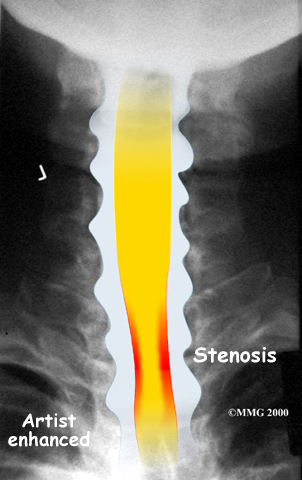

The spinal cord is a column of nerve tissue protected by a bony tube in the spinal column. Conditions that narrow the space in this tube put the spinal cord at risk of getting squeezed. This narrowing is called stenosis. When the narrowing occurs in the spinal column of the neck it is called cervical spinal stenosis, or cervical stenosis. Pressure against the spinal cord as a result of spinal stenosis causes injury to the spinal cord, which is termed myelopathy. Myelopathy is a condition that demands medical attention as it can cause serious problems including problems with the bowels and bladder, changes in the way you walk, and can affect your ability to use your fingers and hands.

The bony spinal canal normally has more than enough room for the spinal cord. Typically, the canal is just less than ¾ of an inch, or 17-18 millimeters around, which is less than the size of a small bottle cap. Spinal stenosis occurs when the canal narrows to around half an inch, or 13 millimeters or less. When the size drops even further, severe symptoms of myelopathy occur. The symptoms of myelopathy result from the actual pressure against the spinal cord itself as well as the reduced blood supply in the spinal cord as a result of the pressure.

Degeneration is the most common cause of spinal stenosis. Wear and tear on the spine from normal aging and from repeated stress and strain can cause many problems in the cervical spine. The intervertebral disc can begin to collapse, shrinking the space between the vertebrae. Bone spurs (small bony projections) may form that protrude into the spinal canal and reduce the space available for the spinal cord. The ligaments that hold the vertebrae together may become thicker and can also push into the spinal canal. All of these conditions narrow the spinal canal.

X-rays are used to look for the cause of pressure against the spinal cord. X-ray images can show if degeneration has caused the space between the vertebrae to collapse and may show if a bone spur is pressing against the spinal cord.

If more information is needed, a magnetic resonance imaging (MRI) scan may be ordered. The MRI machine uses magnetic waves rather than X-rays to show the soft tissues of the body. This test gives a clear picture of the spinal cord and can show where it is being squeezed. An MRI machine creates pictures that look like slices of the area your healthcare professional is interested in. This test does not require any special dye or a needle.